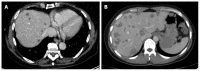

Aim: To establish a computed tomography (CT)-morphological classification for hepatic alveolar echinococcosis was the aim of the study.

Methods: The CT morphology of hepatic lesions in 228 patients with confirmed alveolar echinococcosis (AE) drawn from the Echinococcus Databank of the University Hospital of Ulm was reviewed retrospectively. For this reason, CT datasets of combined positron emission tomography (PET)-CT examinations were evaluated. The diagnosis of AE was made in patients with unequivocal seropositivity; positive histological findings following diagnostic puncture or partial resection of the liver; and/or findings typical for AE at either ultrasonography, CT, magnetic resonance imaging or PET-CT. The CT-morphological findings were grouped into the new classification scheme.

Results: Within the classification a lesion was dedicated to one out of five "primary morphologies" as well as to one out of six "patterns of calcification". "primary morphology" and "pattern of calcification" are primarily focussed on separately from each other and combined, whereas the "primary morphology" V is not further characterized by a "pattern of calcification". Based on the five primary morphologies, further descriptive sub-criteria were appended to types I-III. An analysis of the calcification pattern in relation to the primary morphology revealed the exclusive association of the central calcification with type IV primary morphology. Similarly, certain calcification patterns exhibited a clear predominance for other primary morphologies, which underscores the delimitation of the individual primary morphological types from each other. These relationships in terms of calcification patterns extend into the primary morphological sub-criteria, demonstrating the clear subordination of those criteria.

Conclusion: The proposed CT-morphological classification (EMUC-CT) is intended to facilitate the recognition and interpretation of lesions in hepatic alveolar echinococcosis. This could help to interpret different clinical courses better and shall assist in the context of scientific studies to improve the comparability of CT findings.